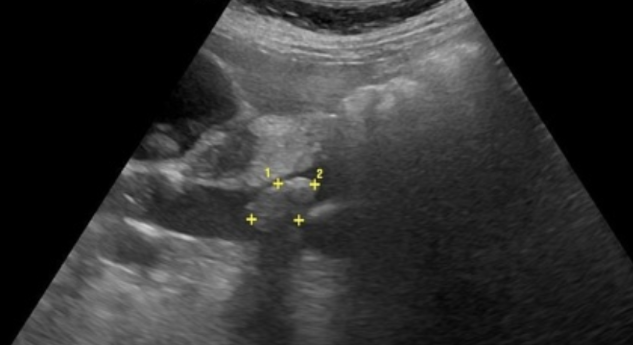

• Dilatation du Cholédoque >6mm (+1mm/10ans)

• Visualisation d’une lithiase (+- Twinkling Artefact)

choledoque